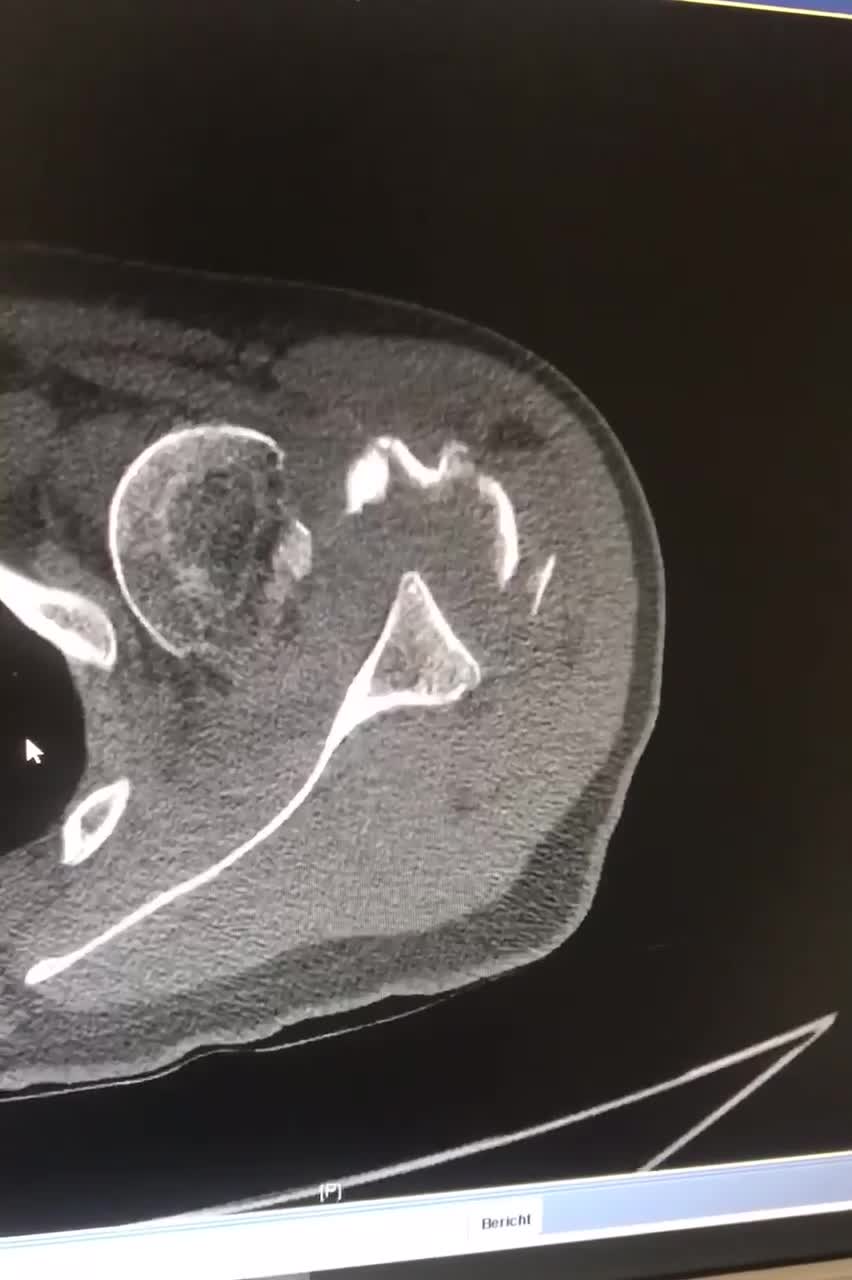

Dr. M. Tanner

Heidelberg University Germany